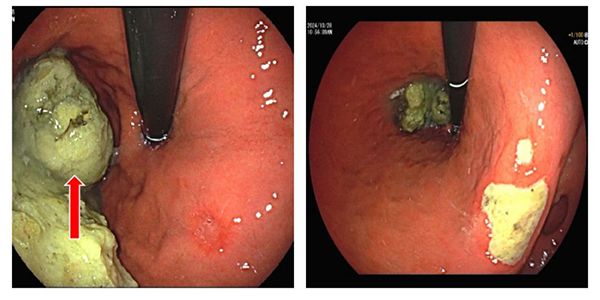

图 2 胃镜下见胃结石 图 3 胃镜下见胃角溃疡